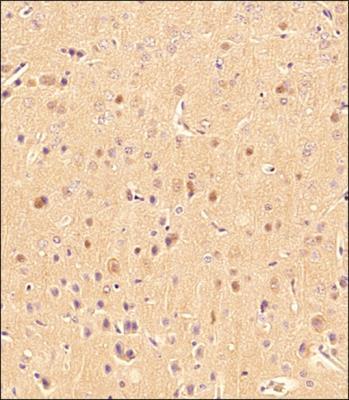

000000001104_xdLkhm2.jpg, NB100-2220 - Novus Biologicals MAP1LC3B antibody | Antibodypediaご覧いただきありがとうございます。アイカツ初期のバインダーになります。母親が管理していたため、未開封かは分かりませんが未使用との事です。その他質問等ございましたらお気軽にコメントお願い致します。即購入〇まとめ買い〇

NB100-2220 - Novus Biologicals MAP1LC3B antibody | Antibodypediaご覧いただきありがとうございます。アイカツ初期のバインダーになります。母親が管理していたため、未開封かは分かりませんが未使用との事です。その他質問等ございましたらお気軽にコメントお願い致します。即購入〇まとめ買い〇